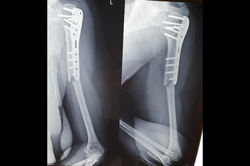

Proximal Tibia

Tibia Nailing